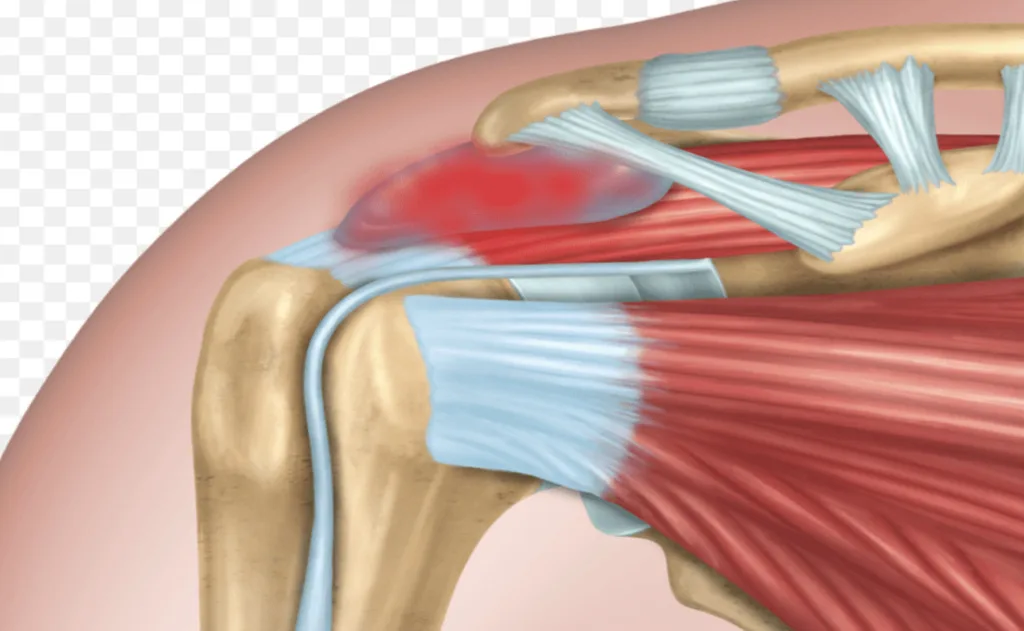

Smrznuto rame, to jest ukočeno rame (poznato i kao adhezivni kapsulitis) je stanje koje uzrokuje bol, ukočenost i ograničene pokrete u ramenu. Najčešće se javlja kod osoba između 40 i 60 godina starosti, a češće pogađa žene nego muškarce. Smrznuto rame nastaje kada se zglobna čahura ramena zadeblja i postane neelastična, što dovodi do smanjenog raspona pokreta i jakih bolova.

Uzroci smrznutog ramena

Iako uzroci nisu uvijek jasni, neki faktori povećavaju rizik za razvoj ovog stanja:

povrede ramena ili operacije

duže mirovanje ruke zbog gipsa ili imobilizacije

bolesti poput dijabetesa, srčanih oboljenja ili poremećaja štitnjače

autoimune bolesti

Dijagnoza i liječenje

Liječnik postavlja dijagnozu na osnovu simptoma i pregleda, a ponekad se koristi rendgen ili magnetna rezonanca kako bi se isključili drugi problemi. Liječenje obično uključuje fizikalnu terapiju, lijekove protiv bolova i vježbe. U težim slučajevima može se preporučiti injekcija kortikosteroida ili operativni zahvat.